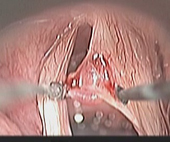

喉部顯微手術的過程其實非常簡單。首先,為了減少手術過程中的不適,患者需要接受短暫的全身麻醉。之後醫師會使用硬式的『喉直達鏡』(圖一),將會厭軟骨挑起並固定支撐後即可清楚的看到聲帶的全貌。跟一般門診使用的喉部內視鏡比起來(圖二,象牙白色直直的兩條即為聲帶),經過手術顯微鏡放大4-10倍之後,所有的聲帶病變均無所遁形,無論是聲帶表層常見的長繭(圖三,雙側聲帶長繭),或是聲帶息肉,都可以藉由特製的精細長柄器械,在顯微鏡下操作切除(圖四),以恢復聲帶平整的外觀。

圖一、喉直達鏡在病人麻煩下的固定情況,讓手術能輕易穩定的進行。